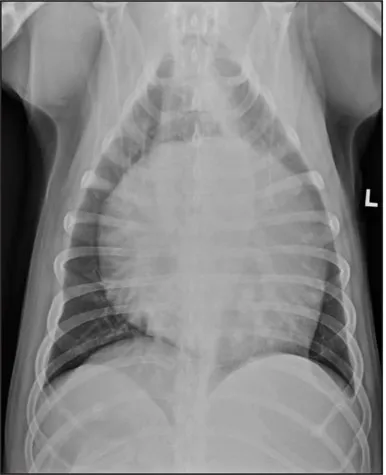

CASE 1.1 A 7-year-old neutered male Labrador Retriever who was hit by a car. You obtain these thoracic radiographs: Figs. 1.1a, b, left and right lateral projections, respectively; Figs. 1.1c, d, ventrodorsal and dorsoventral projections, respectively.

1.1a

1.1b

1.1c

1.1d